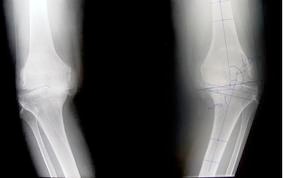

Modern techniques using patient specific instruments or Computer Aided Navigation techniques can improve accuracy compared to traditional techniques. This may improve the length of time the implant lasts for.